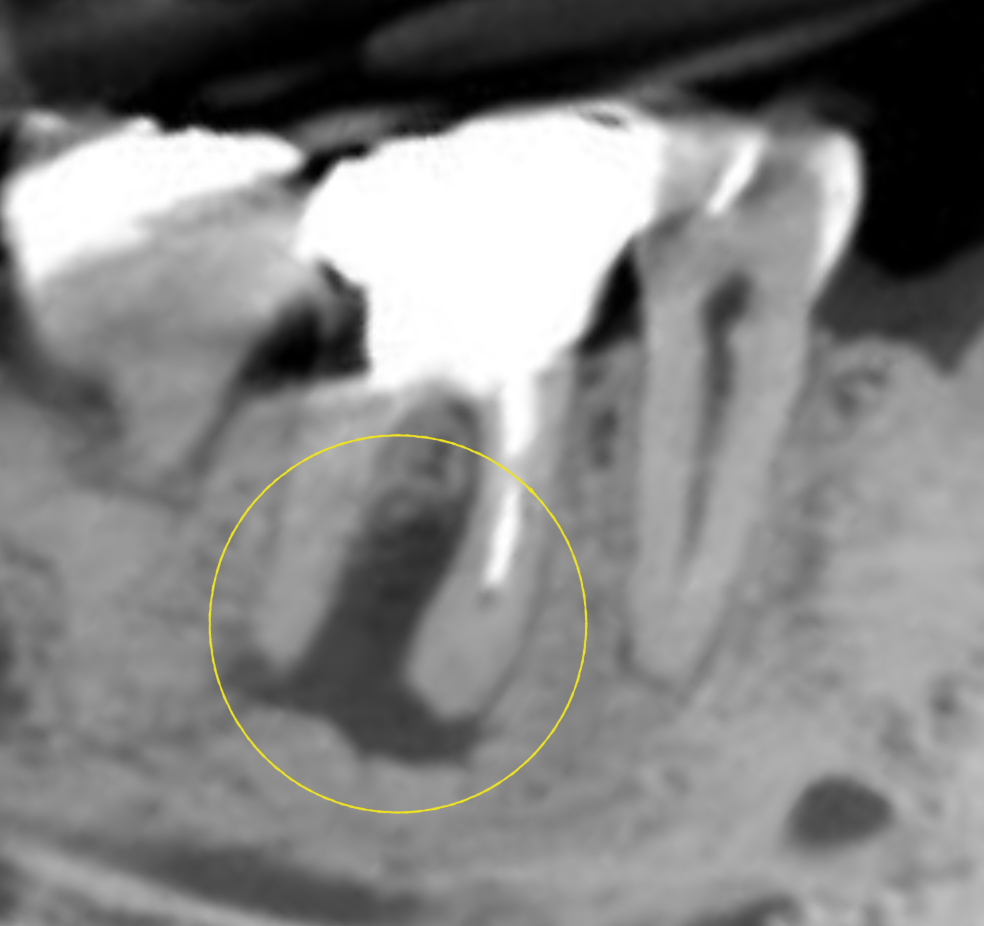

CT画像から判断するに

頬側の骨が破壊されておらず、フラップを開けても病変は出て来ない。

骨頂部から、根尖までは10mm程度とやや長い。